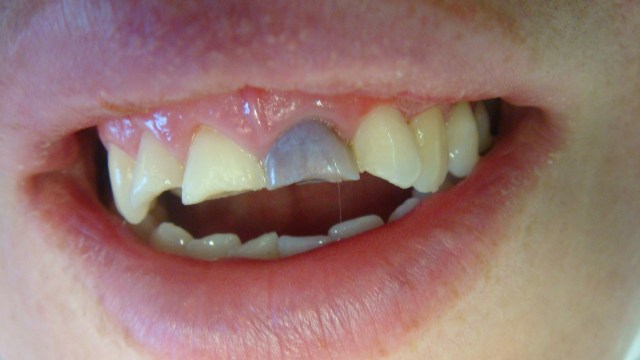

This patient presented a few weeks following a fall where all four Maxillary incisors were damaged. The delay in presentation was due to her upper lip being extremely swollen and painful that she did not want any sort of examination of her dentition.

As shown above the maxillary left central incisor has a complex dentine-enamel fracture and has devitalised. The Maxillary right central incisor also has a complex dentine-enamel fracture. Both lateral incisors have dentine enamel fracture with no pulp exposure and were extremely sensitive to air.